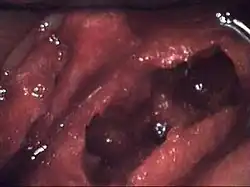

Osteonecrosis of the jaw of the upper left jaw in a patient diagnosed with chronic venous insufficiency | |